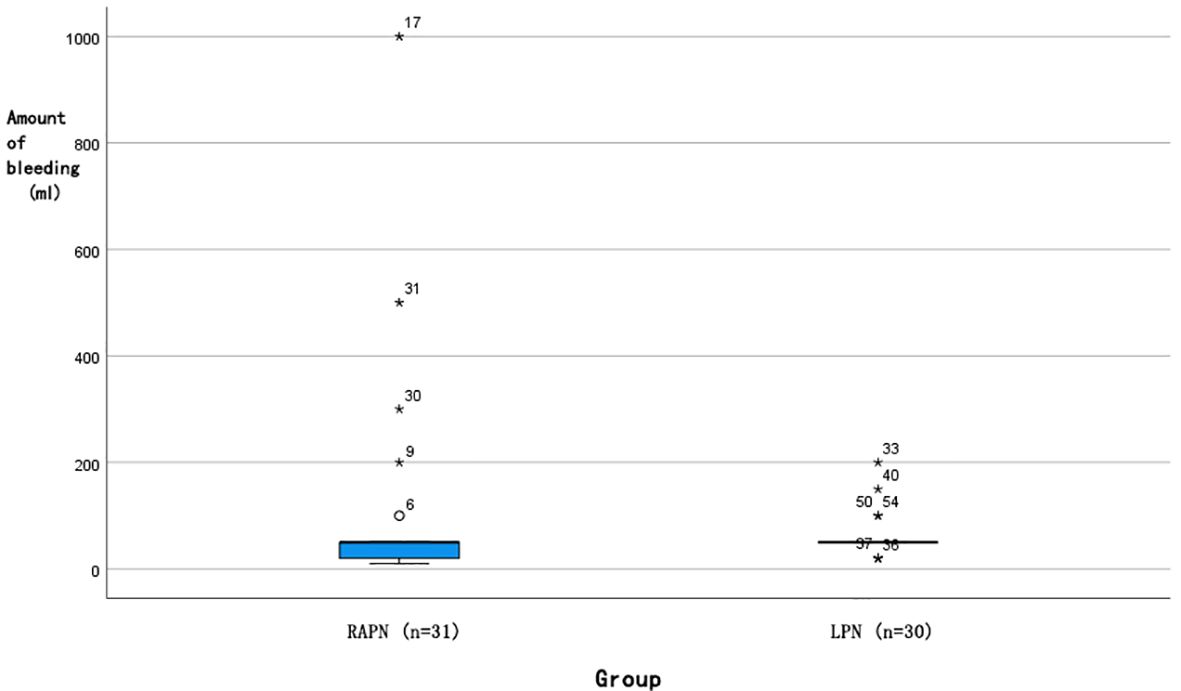

Each group had one case converted to radical nephrectomy due to significant intraoperative bleeding. No statistically significant differences were observed in operative time [145 (126, 193) min vs. 133 (115, 163) min, P=0.103] or postoperative hospital stay [7 (6, 7) days vs. 7 (5, 7) days, P=0.105]. Analysis of intraoperative blood loss revealed a more favourable distribution in the RAPN group (Figure 5), with a median of 50 [IQR 20–50] mL, where 25% of cases had ≤20 mL, compared to the LPN group’s median of 50 [IQR 50–50] mL, with a minimum of 50 mL (Mann-Whitney U test, P=0.028). The RAPN group also demonstrated significantly shorter warm ischemia time [20 (20, 25) min vs. 25 (20, 30) min, P=0.037], with an absolute difference of 5 min (95% CI: 1.2–8.8). In the RAPN group, three perioperative complications occurred, all managed successfully: one Grade IIIa (renal vascular rupture treated with arterial embolization), one Grade II (suspected internal haemorrhage with platelet count of 30×10^9/L and haemoglobin of 66 g/L, treated with transfusion), and one Grade II (chylous leakage managed with nutritional support). The LPN group had two complications: one Grade V (acute myocardial infarction with fatal outcome) and one Grade II (suspected pulmonary embolism treated with anticoagulation). Complication rates did not differ significantly between groups (P>0.05). All malignant tumours were further classified according to the World Health Organization/International Society of Urological Pathology (WHO/ISUP) grading system. In the RAPN group, among the 30 malignant cases, the distribution of WHO/ISUP grades was: Grade 1 (n=4, 13.3%), Grade 2 (n=24, 80.0%), and Grade 3 (n=1, 3.3%); one case of chromophobe renal cell carcinoma (RCC) was not graded by this system. In the LPN group, all 26 malignant cases were classified as Grade 2 (100%); two cases of chromophobe RCC and one case of papillary RCC were not graded. The proportion of benign tumours was comparable between groups (3.2% vs. 13.3%, P = 0.194). All cases achieved negative surgical margins. No significant differences were noted in postoperative eGFR at day 1 [(84.67 ± 22.25) mL/min vs. (87.26 ± 19.92) mL/min, P=0.634] or 3 months [(92.17 ± 30.42) mL/min vs. (95.21 ± 22.91) mL/min, P=0.738]. At a median follow-up of 6 months (range 3-12), no local recurrence or distant metastasis was detected on imaging in either group.

Figure 5. Box plot of intraoperative bleeding distribution for RAPN and LPN surgeries. (█: Median 50 ml; ◯: Outlier; *: P<0.05).

Notably, intraoperative blood loss was significantly lower in the RAPN group, with 25% of cases achieving blood loss ≤20 mL—an outcome not observed in the LPN group where the minimum blood loss was 50 mL. This advantage may be attributed to the improved dexterity and stability offered by the robotic system, enabling finer dissection and more controlled haemostasis during tumour enucleation. The tremor filtration and motion scaling capabilities of the robotic platform likely facilitate precise dissection along the tumour-parenchyma interface, minimizing vascular injury. Froghi et al. (6) also noted a trend toward reduced blood loss in RAPN compared to LPN for small renal masses, although the difference did not always reach significance across all studies. Our cohort, strictly limited to completely endophytic tumours (R.E.N.A.L. score E = 3), may represent a more homogenous and technically challenging population, thereby magnifying the benefits of robotic precision in vascular control.